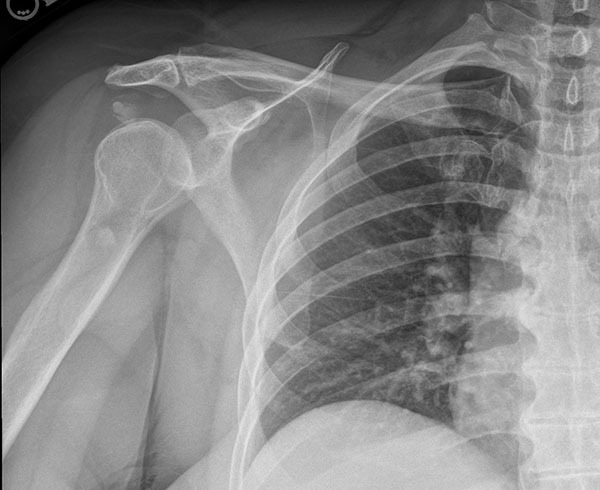

Type III injury results from disruption of the AC and coracoclavicular ligaments with the detachment of the deltoid and trapezius muscles. Vertical or horizontal instability will be present. Type III injuries will have 100% elevation of the clavicle above the acromion and a widened coracoclavicular interspace. (See Figure 2.) Type IV injury is the rupture of all supporting structures with posterior displacement of the clavicle in or through the trapezius. Radiographs in type IV injury may appear similar to a type II or III and often require axillary radiographs to visualize the posterior dislocation of the clavicle. Examination findings include posterior fullness and may include skin tenting.

Figure 2. Left AC Separation |

![]() |

Courtesy of J. Stephan Stapczynski, MD. |